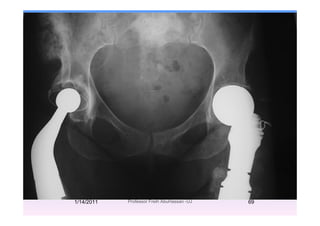

Endoprosthetic SurgeryEndoprosthetic Surgery

E t i d t ti f j l bExtensive destruction of major long bones,

particularly in the metaphyseal regionp y p y g

(hip, knee,)

Custom or modular endoprosthesesp

(‘megaprostheses’)